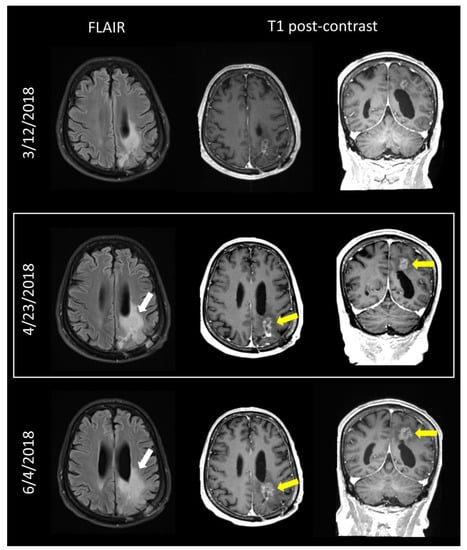

- Weinberg, B.D.; Gore, A.; Shu, H.G.; Olson, J.J.; Duszak, R.; Voloschin, A.D.; Hoch, M.J. Management-Based Structured Reporting of Posttreatment Glioma Response with the Brain Tumor Reporting and Data System. J. Am. Coll. Radiol. 2018, 15, 767–771. [Google Scholar] [CrossRef]

- Gore, A.; Hoch, M.J.; Shu, H.G.; Olson, J.J.; Voloschin, A.D.; Weinberg, B.D. Institutional Implementation of a Structured Reporting System: Our Experience with the Brain Tumor Reporting and Data System. Acad. Radiol. 2019, 26, 974–980. [Google Scholar] [CrossRef] [PubMed]

- Zhang, J.Y.; Weinberg, B.D.; Hu, R.; Saindane, A.; Mullins, M.; Allen, J.; Hoch, M.J. Quantitative Improvement in Brain Tumor MRI Through Structured Reporting (BT-RADS). Acad. Radiol. 2020, 27, 780–784. [Google Scholar] [CrossRef]

- Kim, S.; Hoch, M.J.; Peng, L.; Somasundaram, A.; Chen, Z.; Weinberg, B.D. A brain tumor reporting and data system to optimize imaging surveillance and prognostication in high-grade gliomas. J. Neuroimaging 2022, 32, 1185–1192. [Google Scholar] [CrossRef] [PubMed]